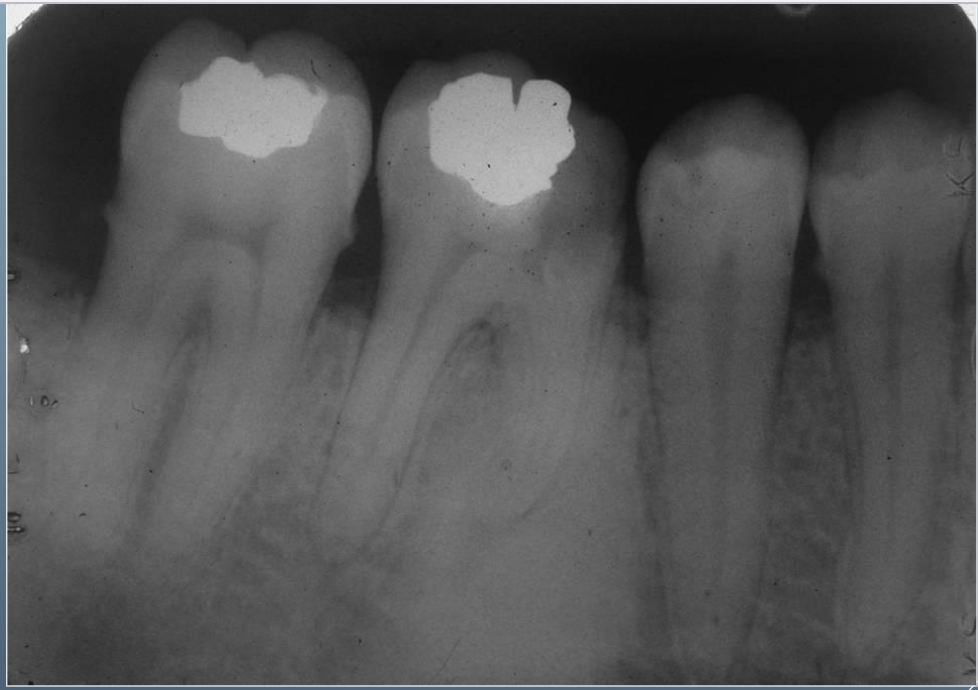

8

Q

What’s this?

A

HEMATOPOIETIC BONE MARROW DEFECT

FOCAL OSTEOPOROTIC BONE MARROW DEFECT

9